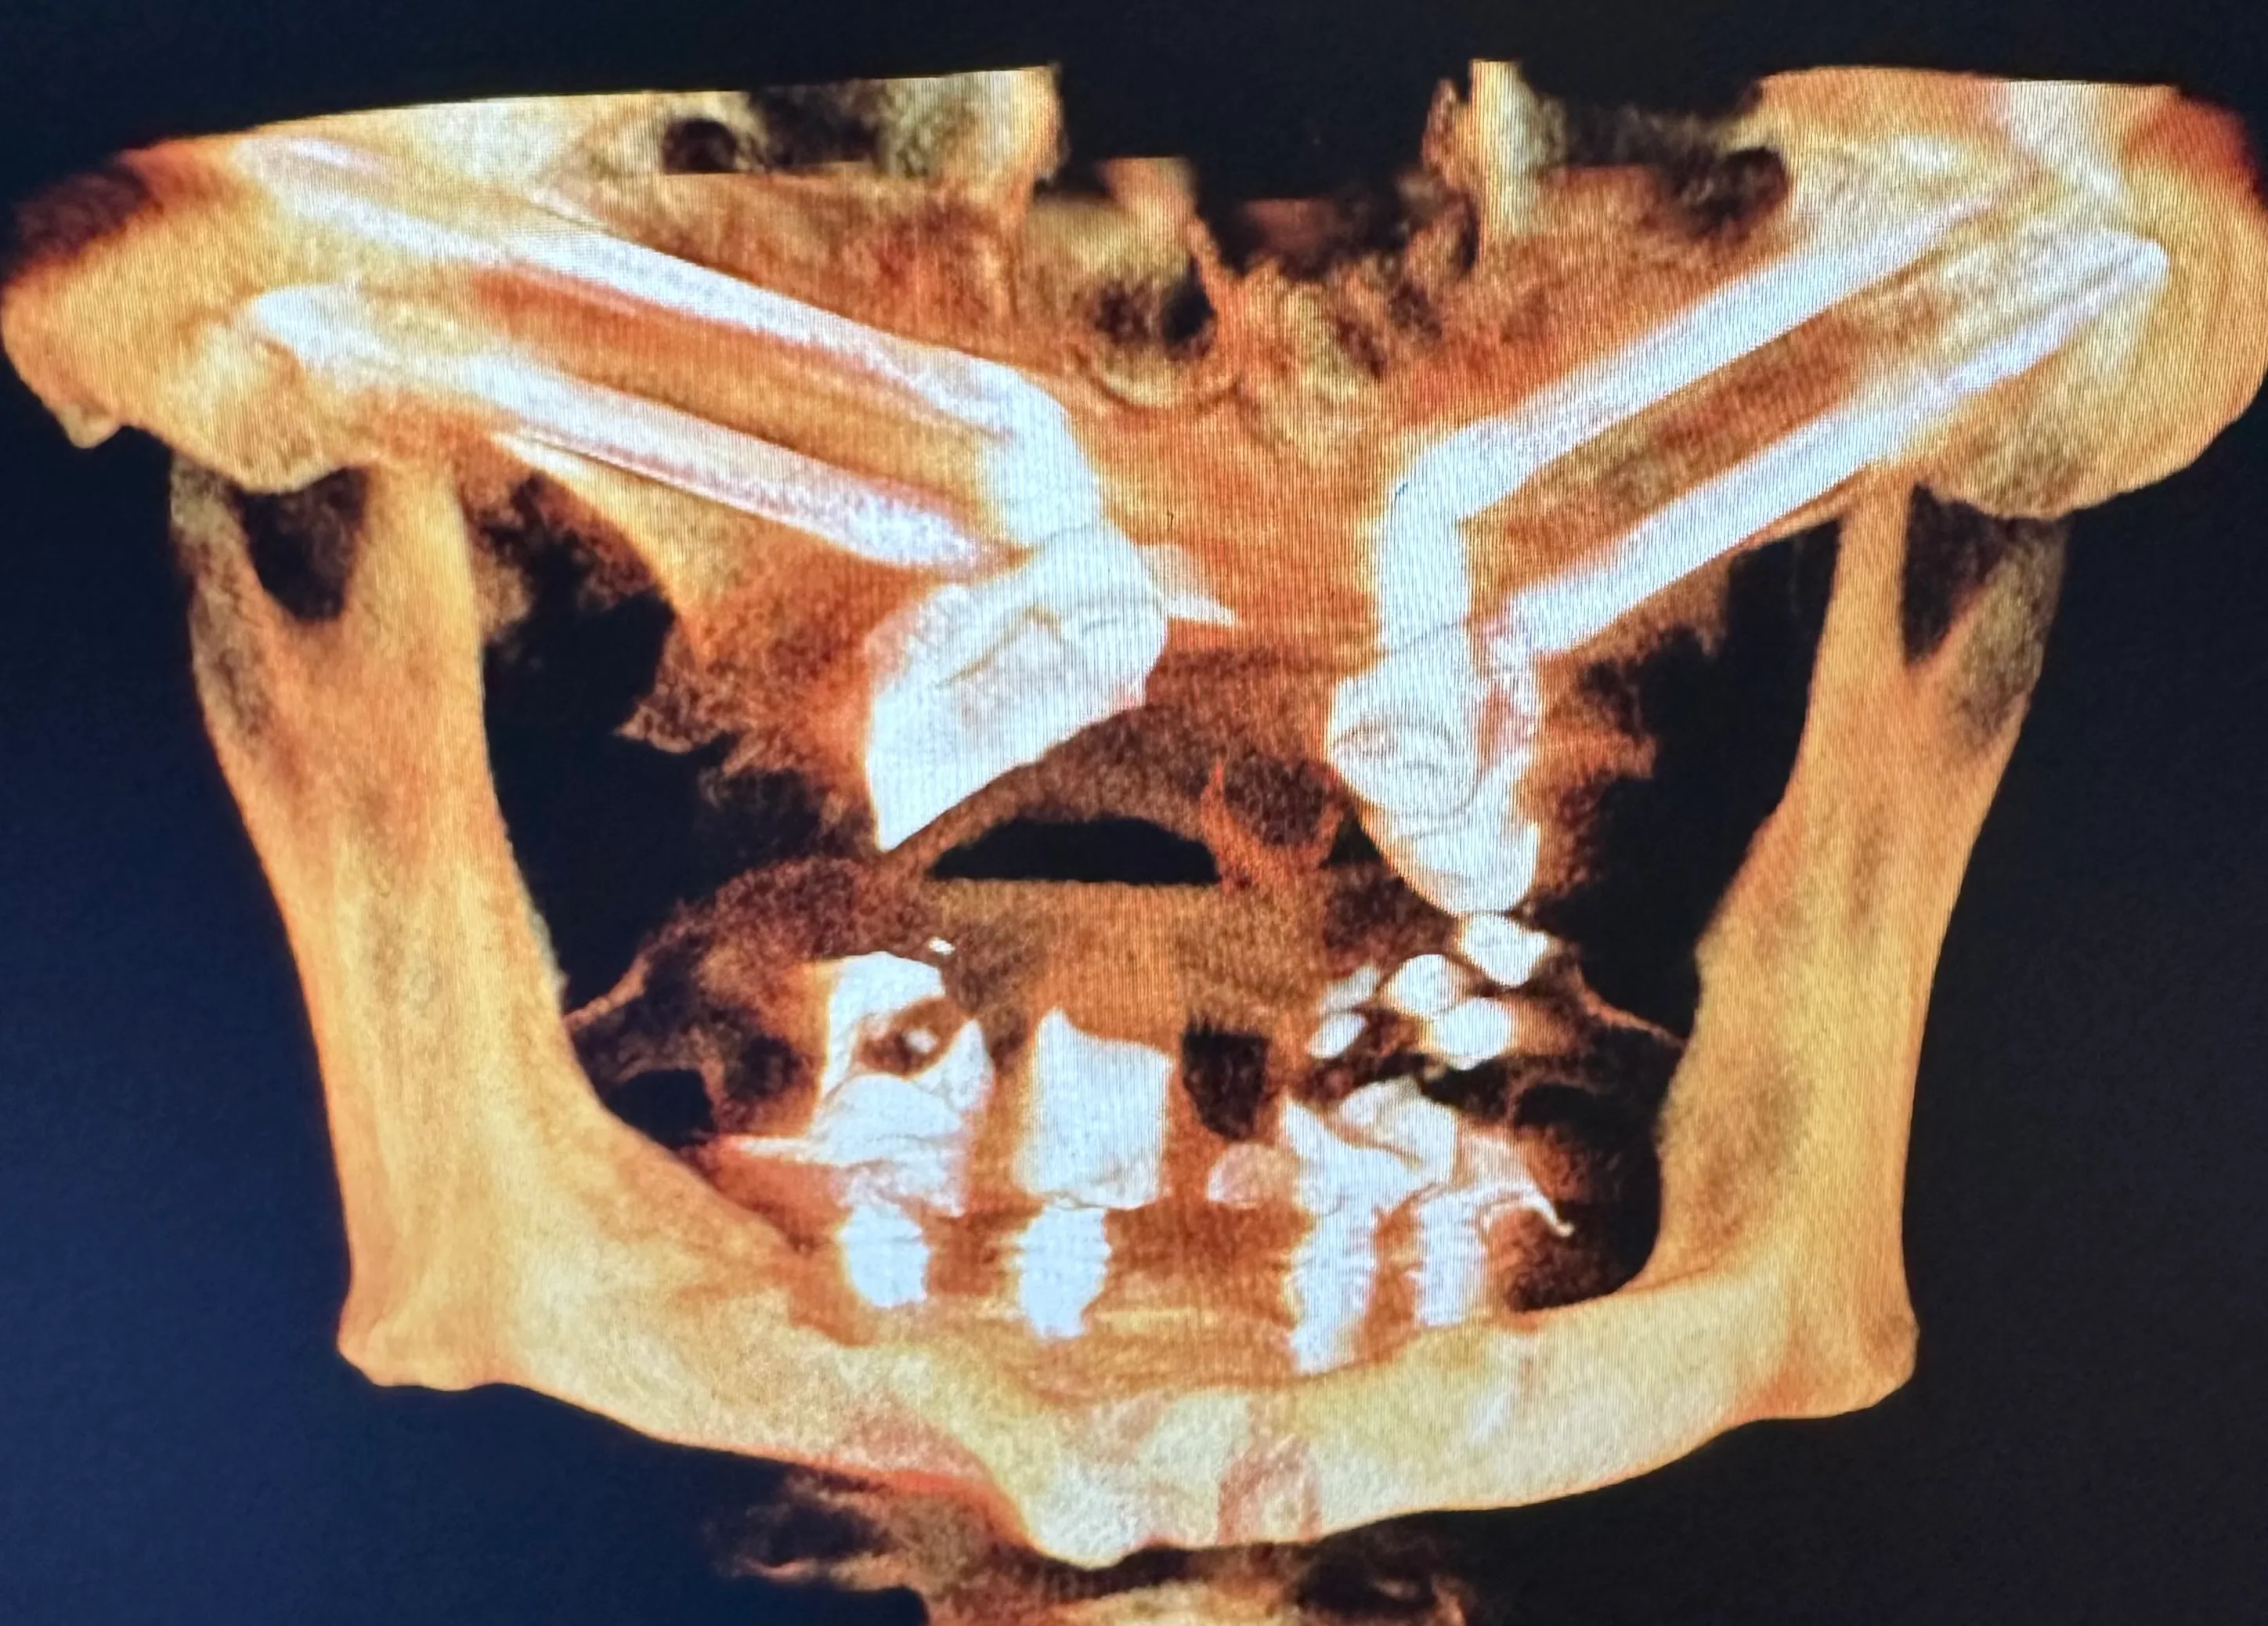

X-ray image of a jaw with dental implants and surgical plates, highlighting the alignment of teeth and orthopedic hardware.

Some patients need only one or two dental implants, while others are completely edentulous (missing all teeth). As with other well-known implant-supported denture options, zygoma implants can support a full arch of prosthetic teeth on just four screws without bone grafting.

Normally, implants are placed in the maxilla to replace missing teeth in the upper jaw. However, some patients have such severe bone loss that there isn’t enough to place an implant safely. In this case, longer implant screws can be used to reach the cheekbones, which are used as an anchor instead.

Zygomatic dental implants are sometimes called “rescue implants” because they can help patients achieve a fully functional bite and aesthetically pleasing smile when bone grafting isn’t possible.